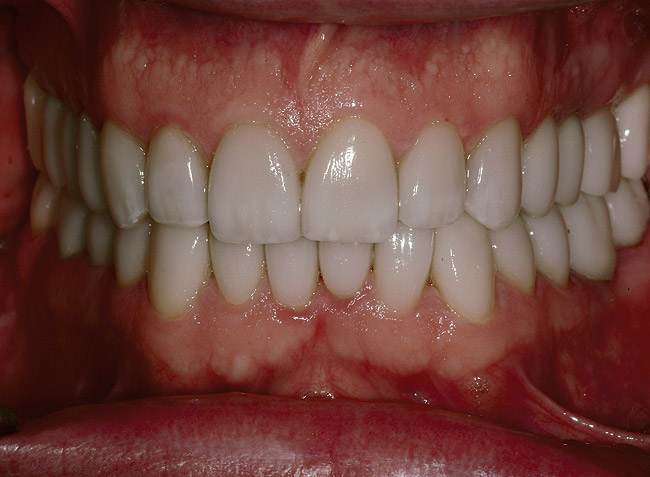

Figure 6  Preoperative retracted view of the dentition.

Figure 6